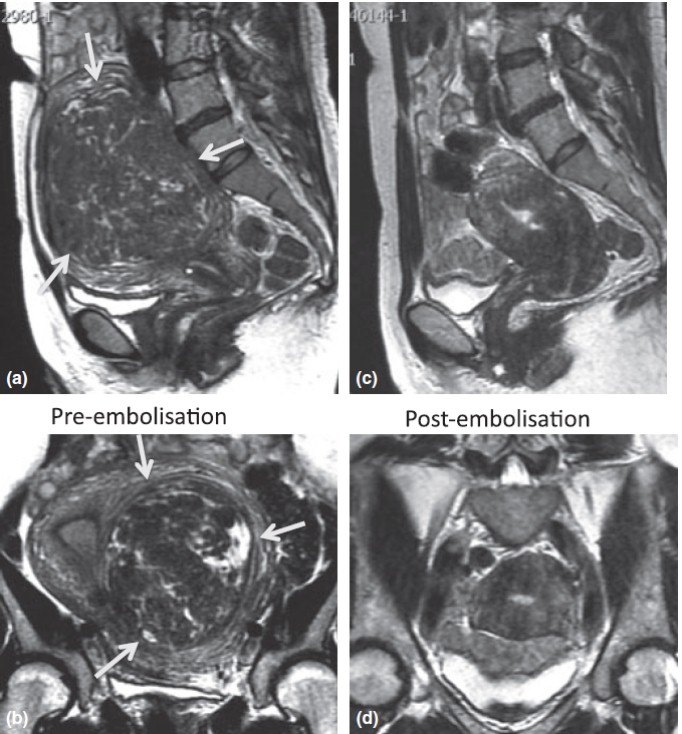

另一病例,同样图a,b为术前子宫肌瘤大小,c,d为术后大小,体积从1300ml减小到129ml。